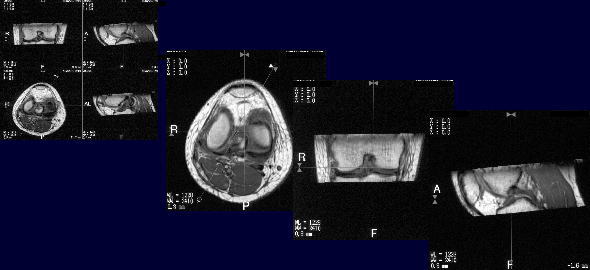

| 幚尡偦偺俁丗儃儔儞僥傿傾偱偺忦審専摙 僼傽儞僩儉偱偺幚尡傪摜傑偊偰丄夋憸僐儞僩儔僗僩偲嶣憸帪娫傪専摙偟偨丅 丂丂丂丂丂丂丂丂  |

| 幚尡偦偺俁丗儃儔儞僥傿傾偱偺忦審専摙 丂丂丂丂丂丂丂丂丂丂嵟廔揑側嶣塭忦審 丂丂丂丂丂丂丂丂丂丂丂丂丂FSE3D10-12(Real-IR 3D) 丂丂丂丂丂丂丂丂丂丂丂丂丂TR/TE=800/10 TI=600 丂丂丂丂丂丂丂丂丂丂丂丂丂FA=90/180 丂丂丂丂丂丂丂丂丂丂丂丂丂NS=40 丂丂丂丂丂丂丂丂丂丂丂丂丂ST=1mm 丂丂丂丂丂丂丂丂丂丂丂丂丂FOV=15cm 丂丂丂丂丂丂丂丂丂丂丂丂丂Matrix=224*224 丂丂丂丂丂丂丂丂丂丂丂丂丂NAQ=1 丂丂丂丂丂丂丂丂丂丂丂丂丂Time=11min11sec 丂丂丂丂丂丂丂丂丂丂丂丂丂Fine Recon&Mid Slice傪巊梡 |

| 亂傑偲傔亃 丒Real-IR朄偱偼崱傑偱3D夋憸偺嶣憸偑弌棃側偭偐偨偑丄崱夞3D僔乕働儞僗傪巊梡偱偒傞傛偆偵側傝ALATOVIEW偺MPR張棟偵偰擟堄抐柺偺娤嶡偑壜擻偵側偭偨丅 丒儖乕僠儞専嵏偱偼昤弌偟偵偔偐偭偨抐柺側偳傕丄3D僨乕僞傪廂廤偟偰偄傟偽嶣憸廔椆屻偱傕 奺昦曄偵懳偟偰昤弌擻偑椙偄抐柺偺娤嶡偑壜擻偲側偭偨丅 丒夋憸嵞峔惉抐柺岤偺擟堄側岤偝偵曄偊傜傟傞偨傔昦曄偵崌傢偣偨嵞峔惉偑壜擻偲側偭偨丅 丒偙傟傜偺寢壥丄嶣憸廔椆屻暋悢偺暋崌昦曄乮敿寧斅懝彎媦傃慜廫帤枵懷丄屻廫帤枵懷懝彎乯偺娤嶡傪偦傟偧傟偺昦曄偵崌傢偣偨抐柺偵傛傞恌抐偑壜擻偲側偭偨丅 |

| 亂寢岅亃 廬棃丄Real-IR朄偱偼俁D嶣憸偑弌棃側偐偭偨偑丄崱夞怴偨偵3D僔乕働儞僗傪巊梡偟ALATOVIEW張棟偵偰擟堄抐柺偺娤嶡偑壜擻偵側偭偨偨傔丄娭愡撪偺昤弌擻偑岦忋偡傞偲巚傢傟偨丅 |